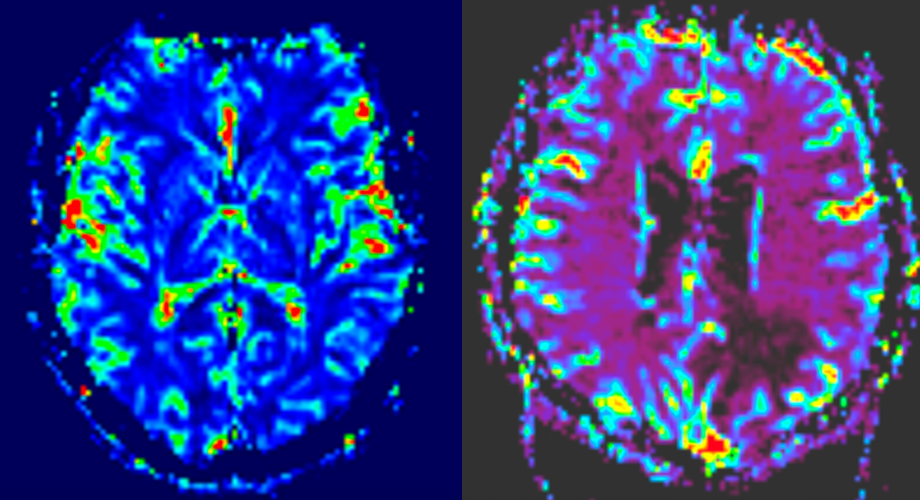

d) RMN de difuzie și perfuzie

- Analizează fluxul sanguin tumoral și gradul de celularitate.

- Sunt utile în diferențierea între tumori de grad înalt și cele de grad scăzut.